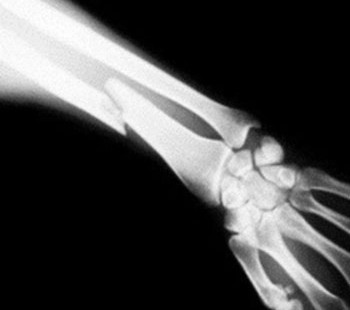

Each year, around 20 million people attend Accident and Emergency and half of them need an X-ray to check for a broken b...